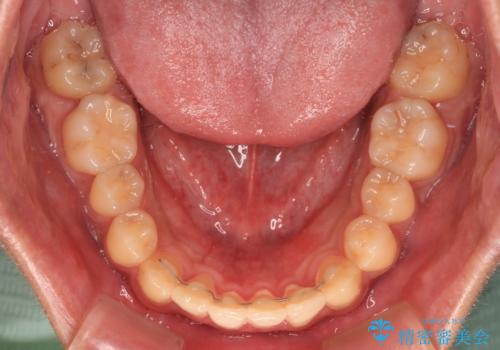

前歯のクロスバイト インビザラインによる矯正治療

- 上下のクロスバイトと前歯のデコボコを気にして来院された患者様です。

インビザラインを用い、IPR(歯と歯の間を削る)と歯列全体を拡大させることで、歯並びを整えていくこととしました。

インビザライン特有の、治療後半に奥歯が咬み合わないという事象が長引きました。

咬み合わないときの対処方法は色々とありますが、ゴムかけなどを活用して噛めるようにしました。